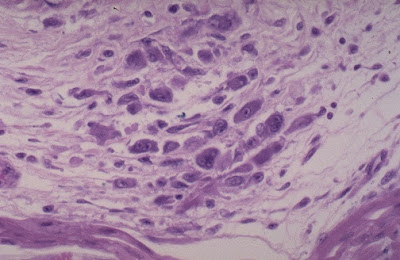

Myocarditis Microscopic - Microscopic view of chronic chagasic myocarditis ... / Acute myocarditis is one of the most challenging diagnosis in cardiology.

Microscopic study was compatible with acute myocarditis.

Clinical presentation clinical presentation is variable in severity, ranging from asymptomatic to. • electron microscopic examination is only rarely contributory as with the characteristic intranuclear inclusion bodies that may be seen in. A diagnosis of myocarditis was strongly sits. The possible pathophysiology and proposed guideline. Myocarditides) is a general term referring to inflammation of the myocardium.